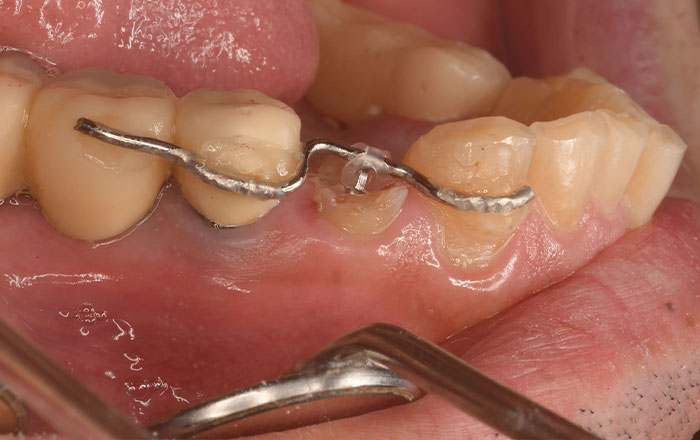

スケーリング(保険適用)

スイス・EMS社製の超音波スケーラーで、歯の表面や歯と歯茎の間にある歯垢や歯石を痛みなく取り除きます。